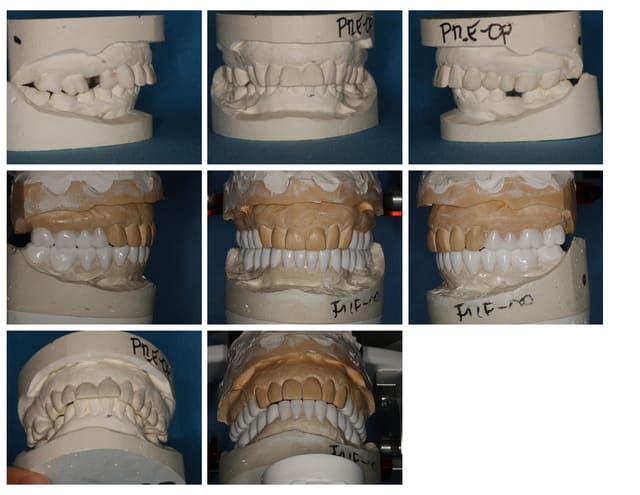

Suite du p'tit cas de ré-hab.

Cirage (wax-up en français ;-))

Gain en vertical et en AP (antéro-postérieur)

Disparition de la Cl-2 par callage postérieur et repositionnement mandibulaire.

Prochaine étape, placer cela en bouche (provisoires).

A suivre...(le cas est en cours, faut être patient)